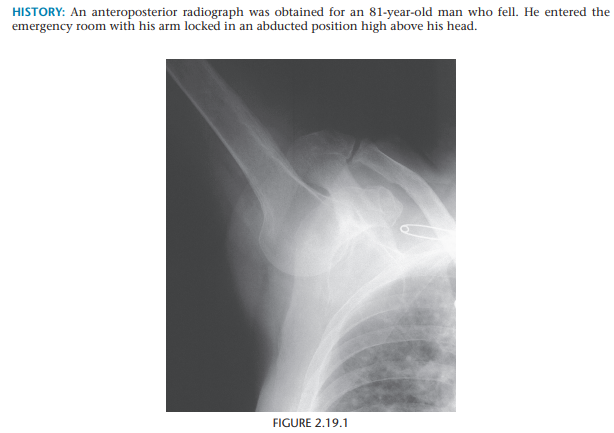

Luxatio Erecta

Fixed elevated position fo the arm - Inferior shoulder subluxation

Brachial plexus and axillary artery injury